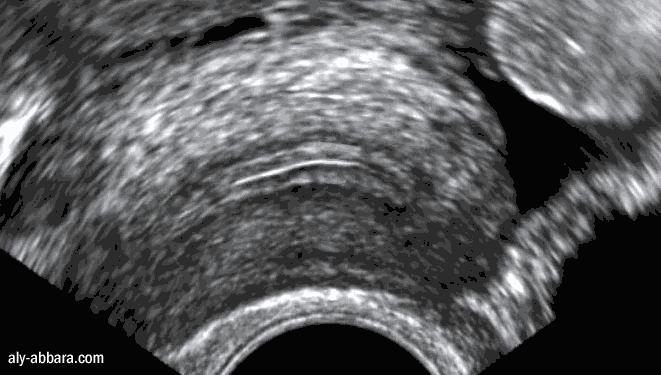

Utérus chez une femme adulte

(première partie du cycle menstruel)

coupe sagittale montrant la technique de mesure de l'épaisseur de l'endomètre